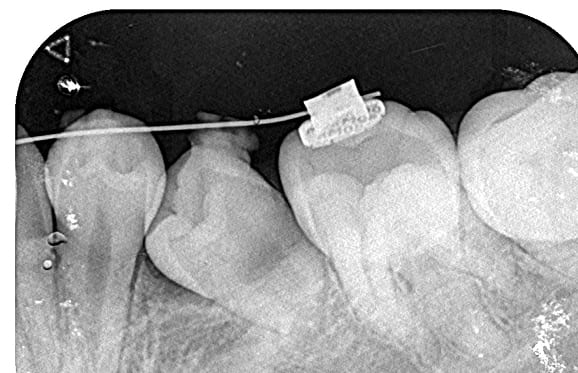

● 症例1

01 左下7の近心根にエンジンファイルの破折

02 ファイル除去時

※根尖周囲の透過像はまだ残存

03 最終の根充剤を充填

※根尖透過像が小さく治癒方向へ向かっている